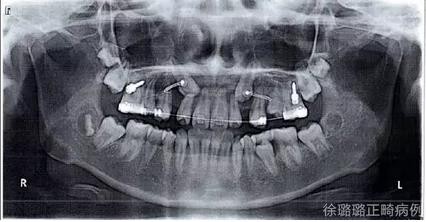

X 線檢查:替牙列,上頜雙側(cè)尖牙埋伏阻生(含牙囊腫),四顆第三恒磨牙牙胚存在。

前牙 CT 檢查:上頜雙側(cè)尖牙埋伏阻生——雙側(cè)尖牙的牙冠均在側(cè)切牙根方的唇向位。

CT 片結(jié)果顯示,上頜雙側(cè)側(cè)切牙與尖牙位置較近,因此早期沒有粘結(jié)雙側(cè)側(cè)切牙托槽,以防止正畸加力對牙齒造成根尖吸收。